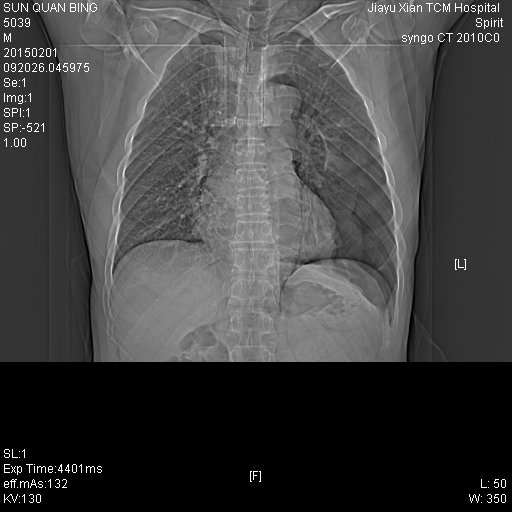

CT49867:患者,男,55岁,因胸痛,胸闷来诊

左侧液气胸并肺不张,肺组织压缩60%以上

左侧气胸 肺膨胀不全,不排除左侧继发性肺结核可能。右侧肺大泡。

左侧液气胸并肺膨胀不全,左下肺病变,多考虑炎性病变。

1.左侧液气胸,左肺压缩80%以上。2.左下肺病变,结核?慢性炎症?其他?3.右肺大疱形成。

左侧肺气肿,左肺膨胀不全,左下肺阻塞性病变?